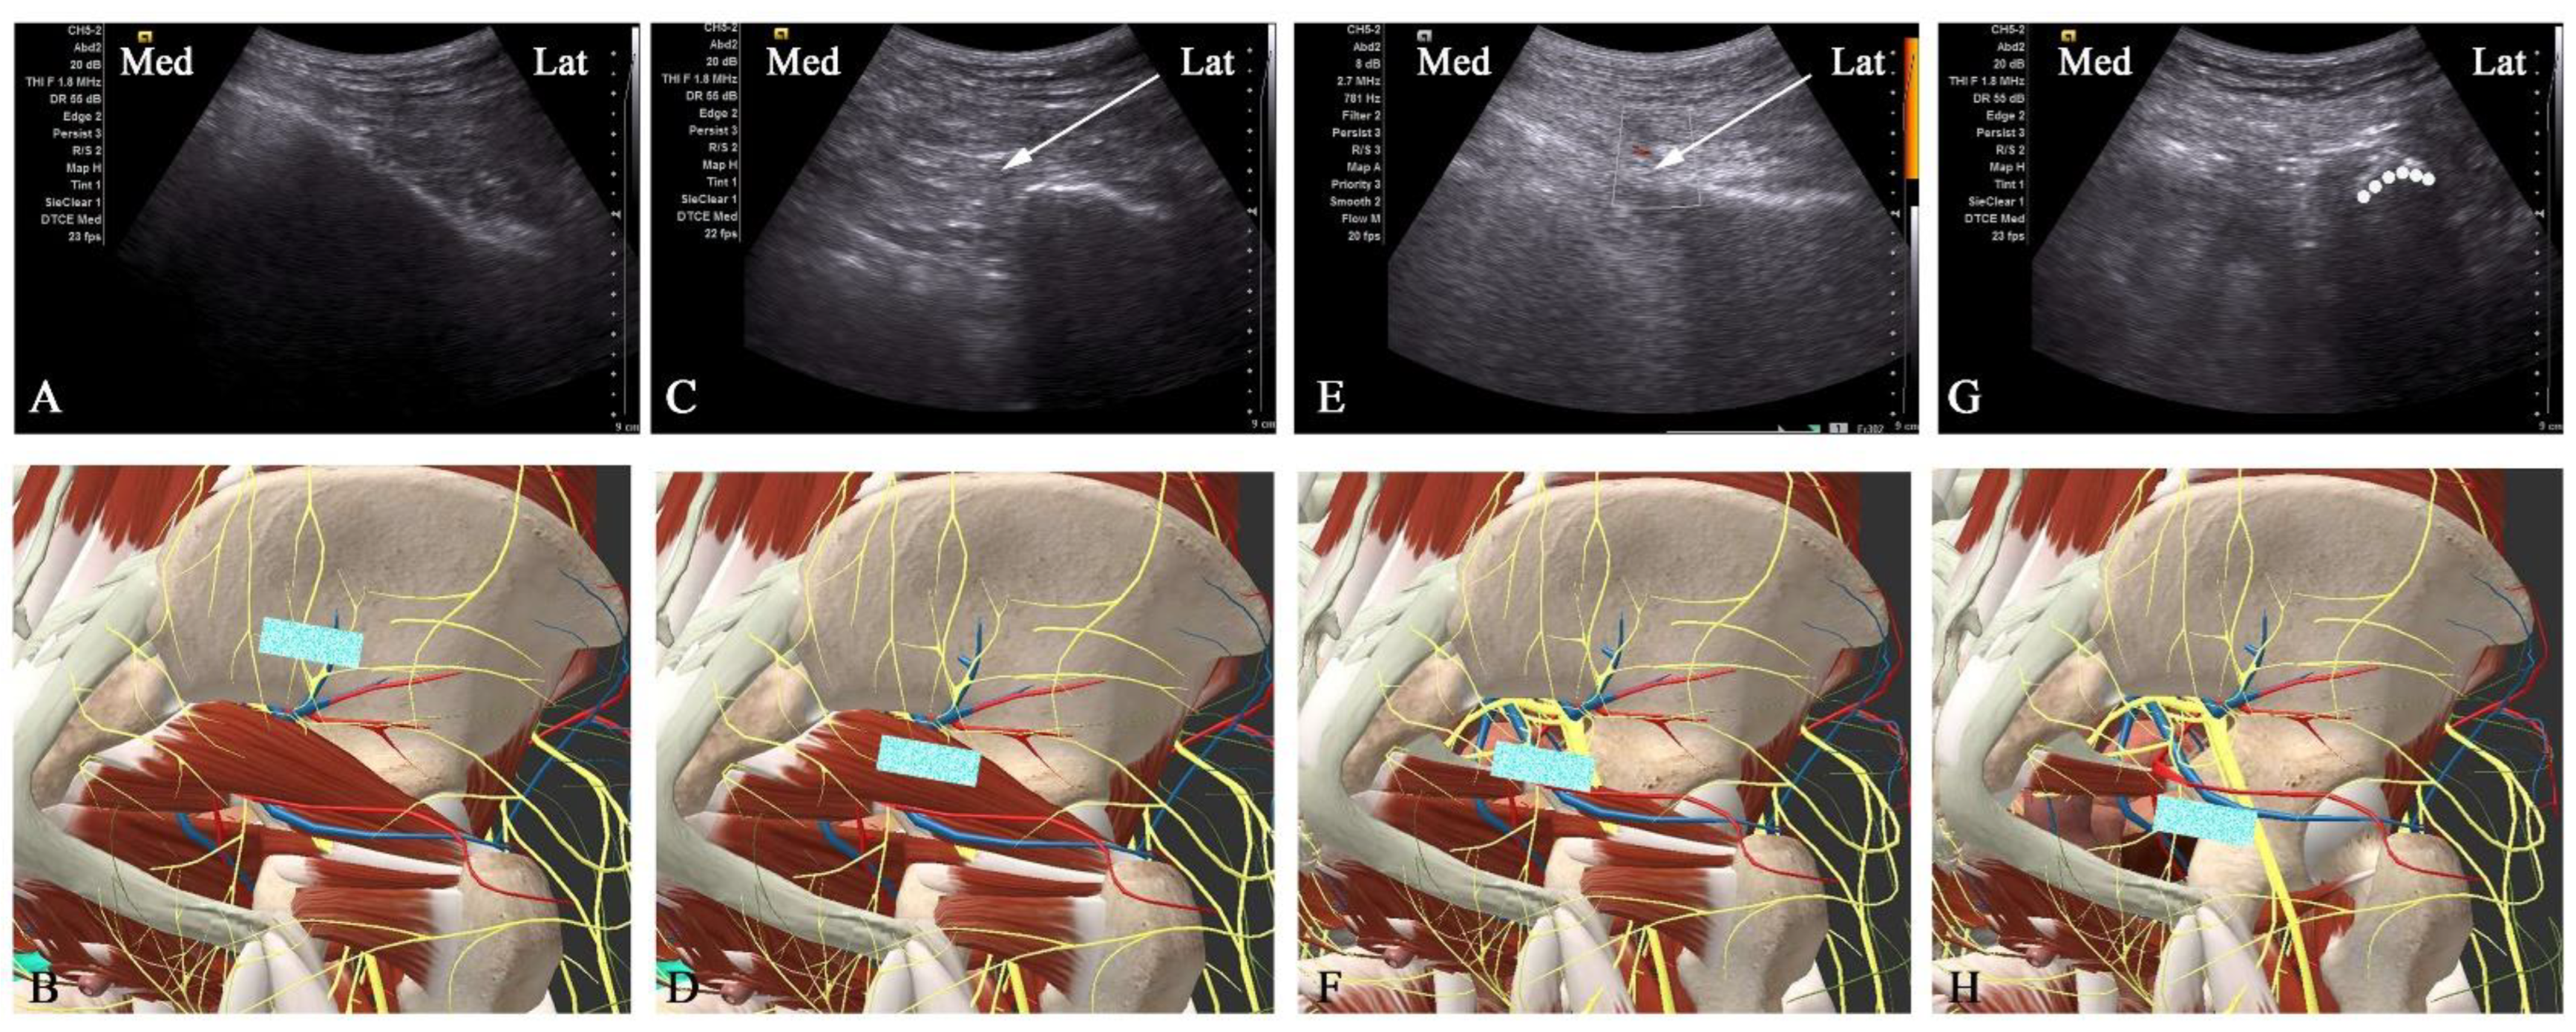

2.3.2. Ultrasound-Guided Improved Pudendal NB Puncture Path Technique